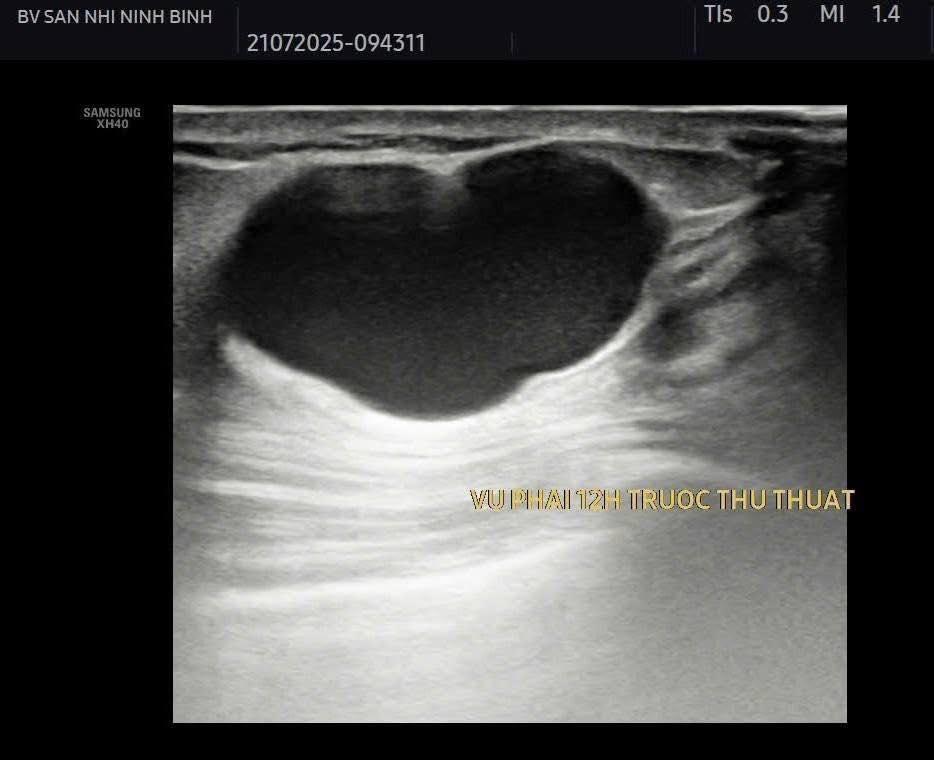

Điều trị diệt nang vú bằng các phương pháp can thiệp tối thiểu như tiêm cồn hoặc các chất gây xơ hóa sau chọc hút nang là phương pháp ít xâm lấn và tỷ lệ tái phát thấp.

Hiện bệnh viện Sản Nhi Ninh Bình đã thực hiện phương pháp điều trị tiêm xơ nang tuyến vú dưới hướng dẫn siêu âm, thực hiện nhanh chóng, thuận tiện ngay tại khoa Chẩn đoán hình ảnh. Giúp bệnh nhân điều trị hiệu quả, tránh tái phát, không cần vào viện và theo dõi tại nhà dưới sự hướng dẫn, dặn dò kĩ càng của bác sỹ điều trị trực tiếp.